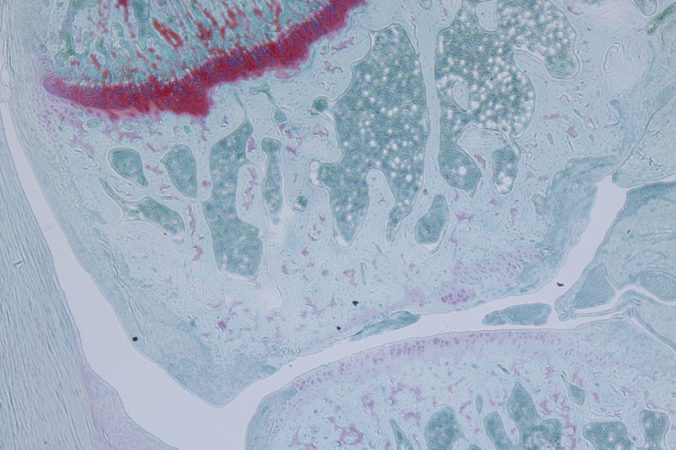

The ability to regenerate joint cartilage cells instead of surgically replacing joints would be a big boon for future patients. (Photo/Nancy Liu, Denis Evseenko Lab, USC Stem Cell)

Human adult articular cartilage has almost no chance of repairing and join surface injuries always results on osteoarthritis which is characterised by loss of matrix, hypertrophy and condrocyte apoptosis. Inflammation mediated by IL-6 family cytokine triggers the expression of matrix degradating enzymes and IL-6 itelf. RCGD423, a small molecule gp130 regulator of cartilage growth and differentiation that promote signalling of receptor. In adult, in vitro work showed that RCGD423 inducing proliferation of chondrocyte but reducing cell apoptosis and hypertrophy response. In rat, RCGD423 improved cartilage healing by enhancing regeneration of cartilage while inhibiting inflammation. Injection of RCGD423 into the knees of rats with damaged cartilage speed up the healing of injuries. Therefore, RCG423 was able to amplify the gp130 receptor to stimulate cartilage degeneration while blocking the inflammatory response.